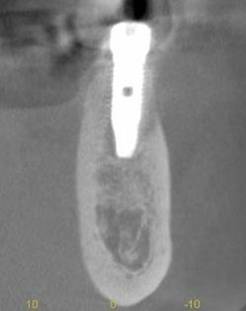

術後のCBCT

インプラントの重大な事故は下顎管から十分な距離をとれば防げます

抜歯部位にインプラントを追加しました。CBCT